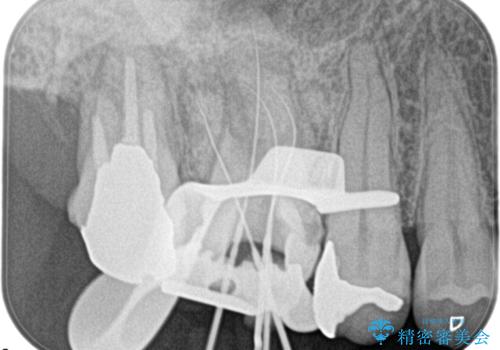

湾曲根管。精密根管治療

検査の結果、右上第一大臼歯の診断を、歯髄壊死とし抜髄を行っております。

湾曲根管に対してエラーなく処置を行えております。